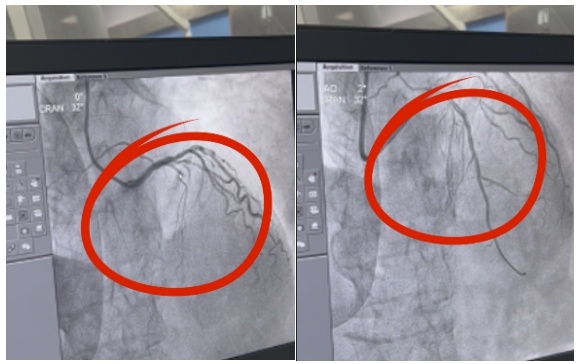

9点02分,120救护车抵达东山卫生服务中心,送往台州市中心医院胸痛中心进行救治。救护车抵达台州市中心医院胸痛中心后,医务人员给患者进行简单且必要的处置,马上送往导管室行介入治疗。通过冠脉造影,蔡海鹏发现患者的前降支近端完全闭塞,需要紧急开通血管,放入血管支架后,血管的血流恢复到了正常。

“整个流程十分紧凑,东山卫生服务中心的医务人员经过胸痛等相关培训后,对于心肌梗死的早期识别、处置和转诊非常流畅,与我们医院胸痛中心联系紧密。”蔡海鹏说,从首次医疗接触到血管开通的时间是86分钟,病人进医院大门到导丝通过冠脉病变狭窄的时间是57分钟,患者得到了很好的救治,挽救了大量心肌,也挽救了患者生命。